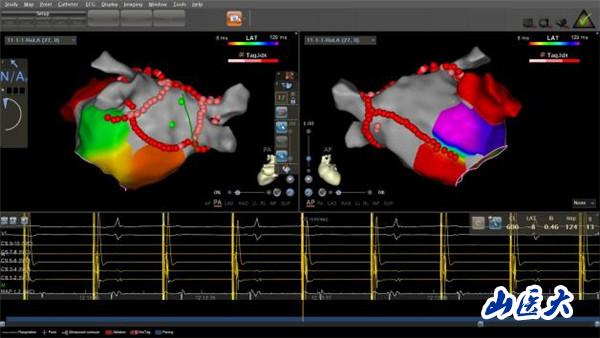

“射頻消融術?就是那種有輻射的手術嗎?”家屬聞此顧慮重重,怕射線給老人的身體帶來更大傷害。王睿主任醫師解釋說,在傳統射頻消融術中,X射線是實現手術可視化的必要條件,如果不借助X射線進行操作,之前射頻消融術是無法實施的。隨著醫學技術的發展,目前采用CARTO(三維電解剖標測系統)開展零X射線下射頻消融術,就像給醫生安了一雙“慧眼”,無須在X射線透視下,即可實現精準導航。這種新技術,在手術過程中放置標測電極和操作消融大頭電極等均采用三維電生理標測系統指導,完全不用X射線透視,卻對手術醫生技術的熟練程度、導管的操作技術以及心臟解剖三維理解要求極高。通過該技術既能獲得準確靶點,縮短手術時間,提升手術安全性,讓患者避免了X線輻射,也讓醫生避免了披“甲”上陣、負重手術,因此被稱為綠色電生理射頻消融術。

經過充分溝通,由王睿主任醫師率領的心電生理團隊在CART0指引下,十分精準地操控導管在患者心臟內走行、檢查、建立模型、精準定位、消融靶點。術中,老人生命體征平穩,無明顯不適。三個小時后,手術順利完成,老人心臟恢復竇性心律,長期困擾其的房顫終于“驅魔”成功。